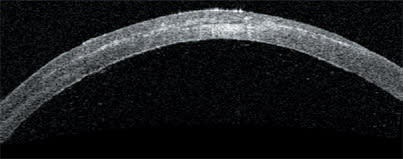

This slide shows Visante OCT measurements of flap and stromal thickness following LASIK. It's clear that the thickness of this flap is not uniform. The measured thickness values range from 140 μm to 183 μm.